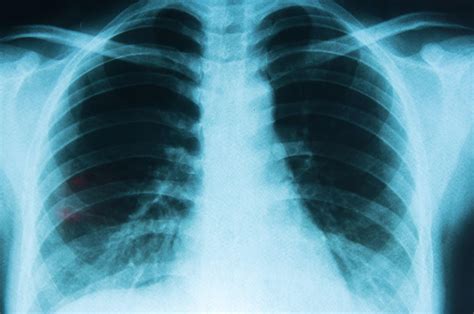

Finding a suspicious spot on your imaging results can be an overwhelming experience. When you receive a report mentioning lung cancer on CT scan, it is natural to feel anxious, but it is important to understand that not every abnormality is cancerous. A computed tomography (CT) scan is a sophisticated diagnostic tool that provides detailed cross-sectional images of the lungs, allowing radiologists to identify nodules, masses, or other irregularities that require further investigation. Understanding how these scans work and what they reveal is the first step in navigating the path toward diagnosis and, if necessary, treatment.

A CT scan uses X-ray technology coupled with computer processing to create detailed images of the organs, bones, and tissues inside your body. Unlike a standard chest X-ray, which provides a two-dimensional view, a CT scan generates a series of thin "slices" that provide a high-resolution, three-dimensional perspective of the lungs. This allows medical professionals to detect small nodules that might be invisible on traditional imaging.

When a radiologist evaluates a scan for lung cancer on CT scan, they are primarily looking for pulmonary nodules. These are small spots of tissue that appear brighter or denser than the surrounding lung tissue. While many nodules are benign—often the result of past infections, inflammation, or scar tissue—some may represent early-stage lung cancer, making timely evaluation critical for effective management.